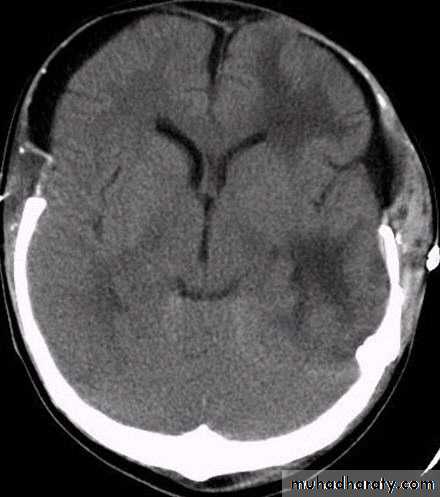

5. Hydrocephalus

a. Acutely due to obstruction of CSF outflow due to intraventricular blood.

b. Delayed post-traumatic communicating hydrocephalus due to impaired CSF reabsorption following traumatic subarachnoid haemorrhage

Intraventricular blood can lead to Hydrocephalus

د.عبدالرحمن